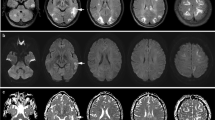

For all patients, involvement of the following nine brain regions was assessed on FLAIR-weighted images by two of the authors in consensus: occipital lobes, parietal lobes, temporal lobes, frontal lobes, basal ganglia, thalami, corpus callosum, cerebellar hemispheres, and pons. In all regions except the corpus callosum, the involvement of each side was evaluated separately. The extent of the abnormal signal in each region was graded on a scale of 0 to 3 (0: normal-appearing brain parenchyma, 1: subtle signal abnormalities that are only faintly visible, 2: large confluent areas of high-signal intensity abnormalities that are easily perceptible, 3: complete involvement of the brain region; Fig. 1). The diffusion-weighted imaging (DWI) studies were searched for the presence of high-signal intensities and, in cases of positive findings, the corresponding ADC values were evaluated.

Measurement of disease extent in the occipital lobe in three different patients. Grade 1 indicates subtle signal abnormalities that are only faintly visible; grade 2 indicates large confluent areas of high-signal intensity abnormalities that are easily perceptible; and grade 3 indicates complete involvement of the brain region

Signal intensity abnormalities on T2-weighted and FLAIR images were bilaterally symmetric in five patients only; in all other patients, asymmetric involvement of at least one brain region was observed. In four female patients and in one male patient with PRES and hypertension, the initial MRI revealed parenchymal hemorrhage [right caudate nucleus (1 cm) with intraventricular extension (#4; Fig. 2), left parietal lobe (0.8 cm; #14), right parietal lobe (2 cm; #28), parietal lobes bilaterally (1 cm, 0.3 cm; #16), left pons (0.4 cm; #30)]. In one patient with PRES and preeclampsia–eclampsia (#26), subarachnoid hemorrhage was present on initial MRI in the right parietal region.

PRES in a 39-year-old patient (#4) with eclampsia 2 days after delivery. a–c FLAIR-weighted images show extensive, bilateral, abnormal signal intensity in the parietooccipital lobes, the pons, the thalamus, the basal ganglia, and the corpus callosum (splenium). The heterogeneous signal in the right basal ganglia is caused by additional intracerebral hemorrhage with intraventricular extension (arrow). Some smaller foci of abnormal signal are present in the temporal and frontal lobes and in the left cerebellum; d diffusion-weighted MRI shows normal to slightly hyperintense signal intensity in the areas of the FLAIR abnormality, indicating “T2 shine through”. The distinct hyperintense area in the right lateral ventricle is due to hemorrhage

On DWI, most patients (n = 22) had edema isointense to normal-appearing parenchyma. In seven patients with PRES and hypertensive conditions, DWI revealed high-signal intensity abnormalities in the cortical to subcortical regions of the frontal and parietal lobes with isointensity to hyperintensity on ADC maps (Fig. 3), and thus represented “T2 shine through effect”. In one patient (#30), an area of restricted diffusion was present in the left cerebellar hemisphere (0.5 cm), indicating progression to ischemic infarction. None of our patient showed tumefactive edema on FLAIR- or T2-weighted imaging.

A 46-year-old female patient (#8) with PRES related to multi-drug abuse. a FLAIR-weighted image shows extensive, rather symmetric, hyperintense signal intensity in the parietal and posterior frontal lobes; b diffusion-weighted MRI shows band-like high signal intensity in the left pre- and post-central gyrus (arrowhead); c ADC map shows normal signal throughout the brain. The areas of high signal in b (arrowhead) do not have low ADC values, as would be expected in the setting of brain ischemia

In all but three patients, more than one brain region was involved (Fig. 4). With regard to the number of affected brain regions, there was a significant difference between patients with and without preeclampsia–eclampsia. The mean number of affected brain regions in patients with preeclampsia–eclampsia was 4.9 ± 1.66 compared to 3.74 ± 1.84 brain regions in patients without preeclampsia–eclampsia (Mann–Whitney U test, p = 0.046).

a, b FLAIR-weighted images in a 14-year-old patient (#20) with PRES, related to cyclophosphamide therapy, show marked frontal and parietooccipital involvement; c, d FLAIR-weighted images in a 29-year-old patient (#2) with PRES, related to preeclampsia–eclampsia, show only subtle involvement of the right occipital lobe (arrow) and marked involvement of the brainstem and the basal ganglia (arrowheads)